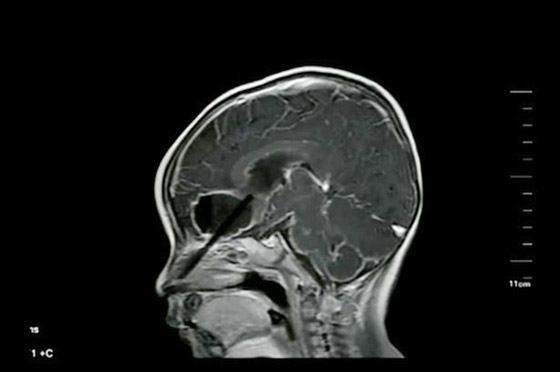

ووفقًا لموقع ميرور، أسرع الأب والأم في نقل الطفل إلى المستشفى وتمكن الأطباء من إزالته وتنظيف الجرح، لكن بعد نحو 10 أيام ظهرت علامات النعاس على الطفل وبدأ في التقيأ وتم نقله مرة أخرى إلى المستشفى وبعد إجراء الأشعة السينية تفاجأ الأطباء عندما وجدوا نحو 6 سنتيمتر من العصا ما زال بداخل رأسه.

وقالت الأم: إنها قامت برمى جميع عيدان الأكل الموجودة بالمنزل بعد زيارتها الأولى للمستشفى خوفًا من تكرار الحادث مرة أخرى لكنها لم تدرك أن ما زال هناك جزء متبقيا بداخل رأس طفلها الصغير.وذكرت التقارير الطبية أنه بمجرد إزالة الجزء المتبقى تحسنت حالة الطفل على الفور ولن يؤثر الحادث على حركات الجسم أو القدرة اللغوية لكنه سيبقى في المستشفى لعدة أيام حتى يتماثل للشفاء.